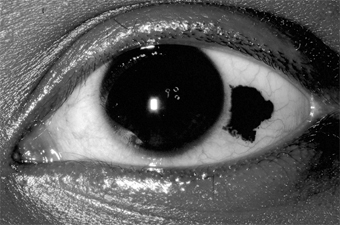

Complications & Sequelae

Conjunctival scarring is a frequent complication of trachoma and can destroy the ductules of the accessory lacrimal glands and obliterate the orifices of the lacrimal gland. These effects may drastically reduce the aqueous component of the precorneal tear film, and the film's mucous components may be reduced by loss of goblet cells. The scars may also cause distortion of the upper lid with inward deviation of individual lashes (trichiasis) or of the whole lid margin (entropion), so that the lashes constantly abrade the cornea. This often leads to corneal ulceration, bacterial corneal infections, and corneal scarring (Figure 5-2).

Figure 5-2

Figure 5-2: Advanced trachoma following corneal ulceration and scarring. Note the fly on the temporal aspect of the lower lid. The fly is a principal vector for trachoma.